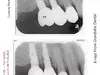

MDA Michigan Dental Association endorsed dentist Dr. Rebecca Vanderbaan & Dr. Larissa Bishop The Past President Of The WMDDS Placed A Dental Crown Tooth #3 Backwards And Wrecked My Restoration.

How did a implant supported crown get placed 180 degrees backwards then get missed then several adjustments to the adjacent teeth were made on four different separate occasions until there was no bite on 8 teeth. Permanent adjustments were made to teeth #5, #6, #7, #26, #27 and #28 all based on a crown tooth number 3 being placed backwards and then let me go with a non-functioning bite.